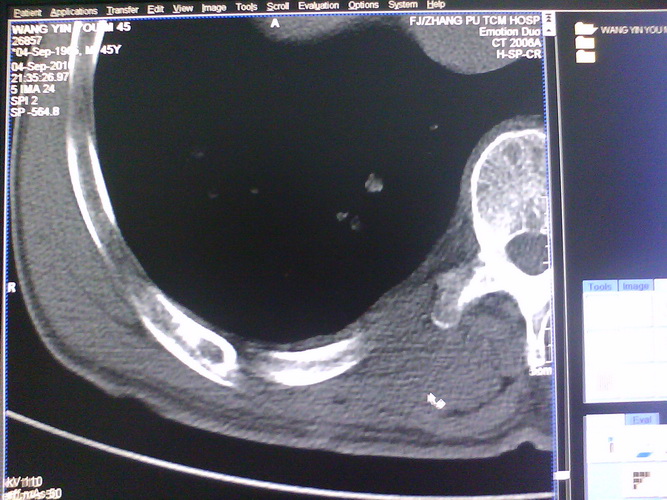

患者,男性,41y,外伤病号,来拍片,发现右侧第9后肋,肋骨膨大,有密度不均,想问大家,是否有问题,要考虑什么东西,谢谢

右侧第九后肋骨纤维结构不良。

支持右侧第九后肋骨纤维结构不良。

考虑骨纤维异常增殖症(混合型)。

肋骨是骨纤好发部位。

骨纤可能性大(肋骨是骨纤好发部位)。